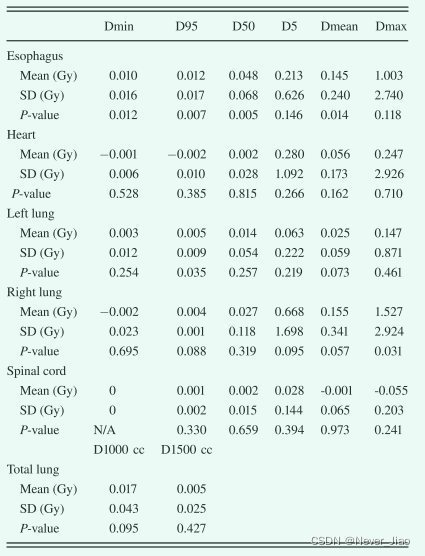

我们还评估了使用所提出的自动分割方法获得的轮廓的剂量影响。如图 7 所示,从手动轮廓获得的示例患者的所有五个 OAR 的 DVH 与所提出的方法匹配良好。 我们计算了从手动轮廓获得的所有五个 OAR 的 Dmean、D95、D50、D5、Dmin 和 Dmax 差异以及所有 20 个计划的建议方法。表 II 总结了基于真实 OAR 剂量和自动分割 OAR 剂量计算的剂量差异的平均值、标准偏差和相应的 P 值。所有 32 个剂量学指标中有 26 个显示 P > 0.05,表明ground truth OAR 和自动分割 OAR 之间没有统计学上显著的剂量差异。所有五个 OAR 的 Dmean、D95、D50、D5 和 Dmin 的平均差异均小于 0.7 Gy。平均 Dmax 差异范围为 0.06 至 1.5 Gy。 全肺D1000 cc和D1500cc的平均剂量差异均小于0.02 Gy,均P>0.05。

Table2. 在20个立体定向身体放射治疗计划中,使用ground truth危险器官 (OARs) 剂量和自动确定的OARs剂量计算的剂量差异和p值的平均值和标准偏差 (SD)